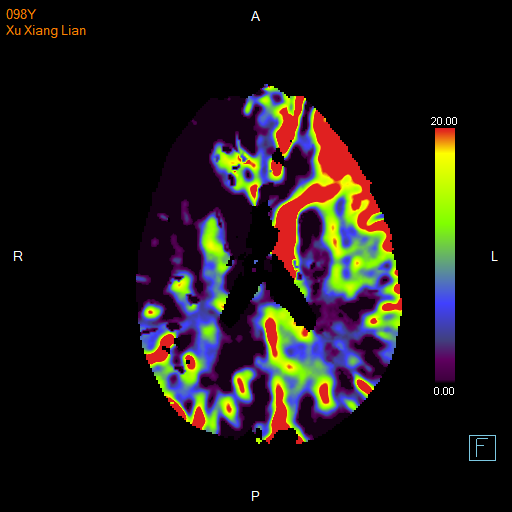

进一步的血管检查(CTA+CTP)发现了更严重的问题:王奶奶的左侧颈内动脉完全闭塞——这是脑梗中最凶险的类型之一,意味着大脑主要供血通道被切断,随时可能危及生命

颅脑 CTP

面对这一严峻挑战,

神经内科介入团队郭钊云医师快速评估后认为:

虽然患者高龄,但发病前身体状况相对稳定,符合急诊动脉取栓术的手术指征,没有手术禁忌症。这是一种通过微创手术直接取出堵塞血管中血栓的先进技术。

与家属充分沟通后,医疗团队决定迎难而上,为王奶奶实施了“取栓支架保护下脑动脉取栓术”,在一个小时内成功将堵塞在左侧颈内动脉及大脑中动脉的大量血栓取出,瞬间恢复了大脑供血。